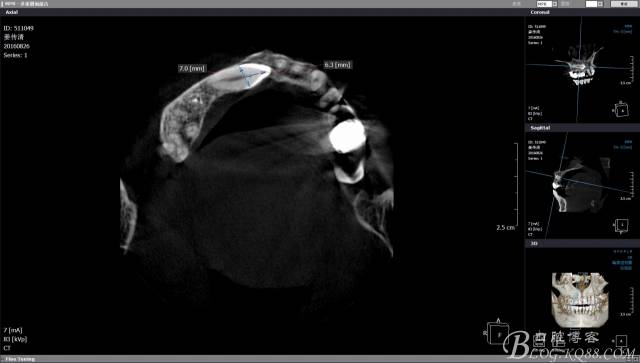

CBCT檢查:A1和A4根尖區(qū)有一水平橫置多生牙,多生牙會影響A1到A4區(qū)域的種植手術(shù),建議外科手術(shù)拔除多生牙。

CBCT檢查尖牙牙冠靠近鼻腭神經(jīng),牙冠靠腭側(cè)且骨皮質(zhì)較薄,牙根靠唇側(cè),雖然走唇側(cè)拔除阻生牙有一個(gè)很好的視野,但是考慮到微創(chuàng)的理念和加上之后會開展種植手術(shù),所以堅(jiān)決不走唇側(cè)去破壞骨皮質(zhì)。

CBCT上模擬T形分壓,測量長度,分離牙冠的時(shí)候長柄裂鉆就是我們手中的尺子,分冠時(shí)候一定切忌老老實(shí)實(shí)按照圖中的7mm去分冠,很容易穿透唇側(cè)骨板,一定要向做上頜竇提升一樣差個(gè)1mm為最合適。